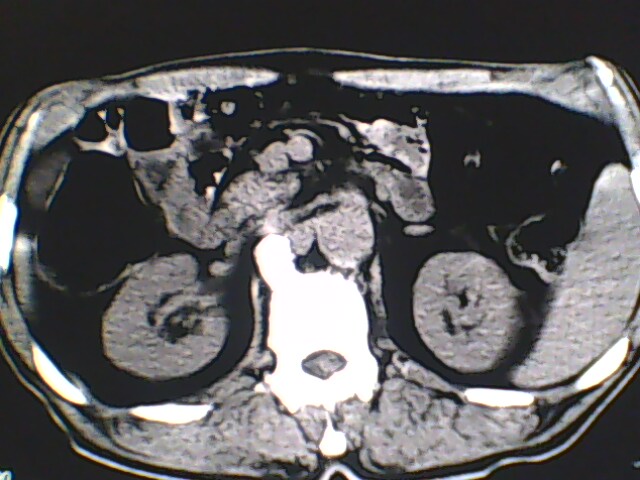

男,56岁,高血压,临床怀疑肾上腺问题,肝脏怎么那么高啊?能描述一下么?

右侧膈膨升,间位结肠,胸腰椎退行性骨关节病,右侧肾上腺可疑增生(图像颗粒太粗,窗太窄,不好看)。

支持 右侧膈膨升,间位结肠;胸腰椎退行性骨关节病;双侧肾上腺可疑增生。